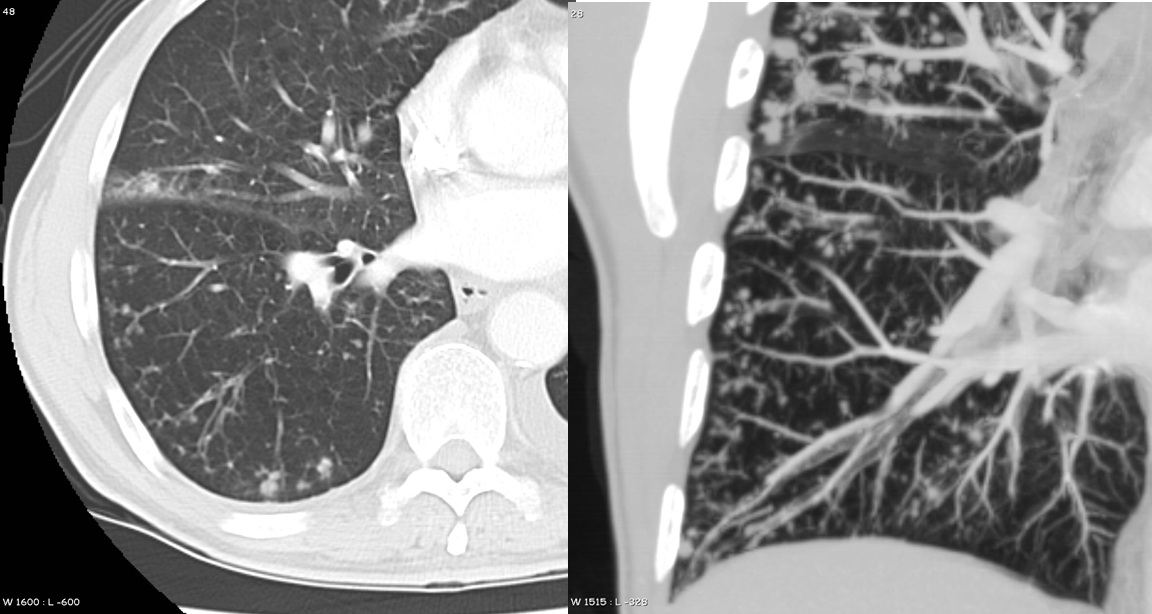

Gallery Pneumonia tree in bud

tree in bud